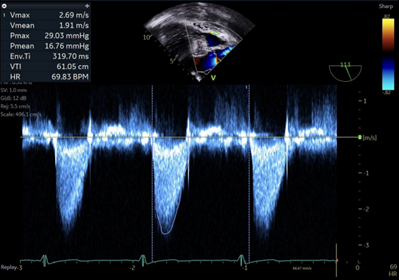

His pre-bypass course and repair are uneventful.  His echo after separating from bypass shows the following:

Image 4

3.  What residual valvular lesion is present?

The residual lesion present is aortic regurgitation. The right-side panel of image 3 shows a color doppler pattern of flow back across the aortic valve into the left ventricle during diastole.

4.  What word can be used to describe the AI jet. What does this mean and what would be the best way or measuring the severity of AI?

This regurgitant jet would be best described as eccentric.  Eccentric aortic regurgitation, in contrast with central aortic regurgitation, is a pattern in which the regurgitant jet does not flow centrally through the aortic valve into the left ventricle, but at an angle.  This angular trajectory may be either due to coaptation geometry (especially in the setting of a bicuspid aortic valve), or defects in the valve leaflets themselves. Measuring severity of regurgitation in the setting of an eccentric regurgitant jet may not allow for some qualitative or semiquantitative measures of regurgitation that include jet density or jet width in the left ventricular outflow tract.  Less direct measures such as pressure half-time and diastolic flow reversal in descending aorta may be necessary.